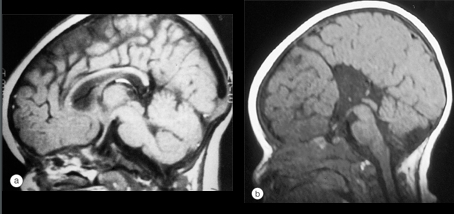

Optic Nerve Hypoplasia

Optic nerve hypoplasia is a condition present from birth in which the eye does not have all the usual wiring between the eye and brain to transfer information about the visual world. The loss of wiring can sometimes be only very small but sometimes can be complete with no information being transferred from the eye to the brain at all. One or both eyes can be affected.

Septo-Optic Dysplasia